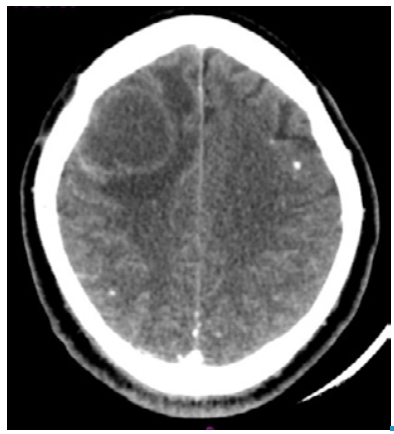

The neurology service requested a computed tomography (CT) that revealed a dilation of the supratentorial ventricular system and a right frontal subcortical cystic lesion that created a mass effect with midline shift. In addition, he presented perilesional edema and small residual bilateral frontoparietal calcifications, suggesting sequelae of NCC (Figure 1). Blood count, C-reactive protein (CRP) and renal function were normal. Pharmacological management was initiated with albendazole at an oral dose of 1600mg every 24 hours, dexamethasone 8mg IV every 8 hours, paracetamol at an oral dose of 1g every 8 hours and omeprazole at an oral dose of 20mg every 24 hours. The patient did not report any side effect caused by these drugs.